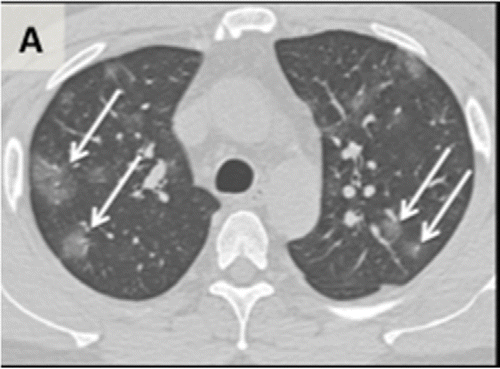

Figure 1a: An axial CT image obtained without intravenous contrast in a 36‐year‐old male (Panel A) shows bilateral ground‐glass opacities in the upper lobes with a rounded morphology (arrows). An axial CT image obtained in a 44‐year‐old male (Panel B) shows larger groundglass opacities in the bilateral lower lobes with a rounded morphology (arrows). An axial CT image obtained in a 65‐year‐old female (Panel C) shows bilateral ground‐glass and consolidative opacities with a striking peripheral distribution.

Figure 1b: An axial CT image obtained without intravenous contrast in a 36‐year‐old male (Panel A) shows bilateral ground‐glass opacities in the upper lobes with a rounded morphology (arrows). An axial CT image obtained in a 44‐year‐old male (Panel B) shows larger groundglass opacities in the bilateral lower lobes with a rounded morphology (arrows). An axial CT image obtained in a 65‐year‐old female (Panel C) shows bilateral ground‐glass and consolidative opacities with a striking peripheral distribution.